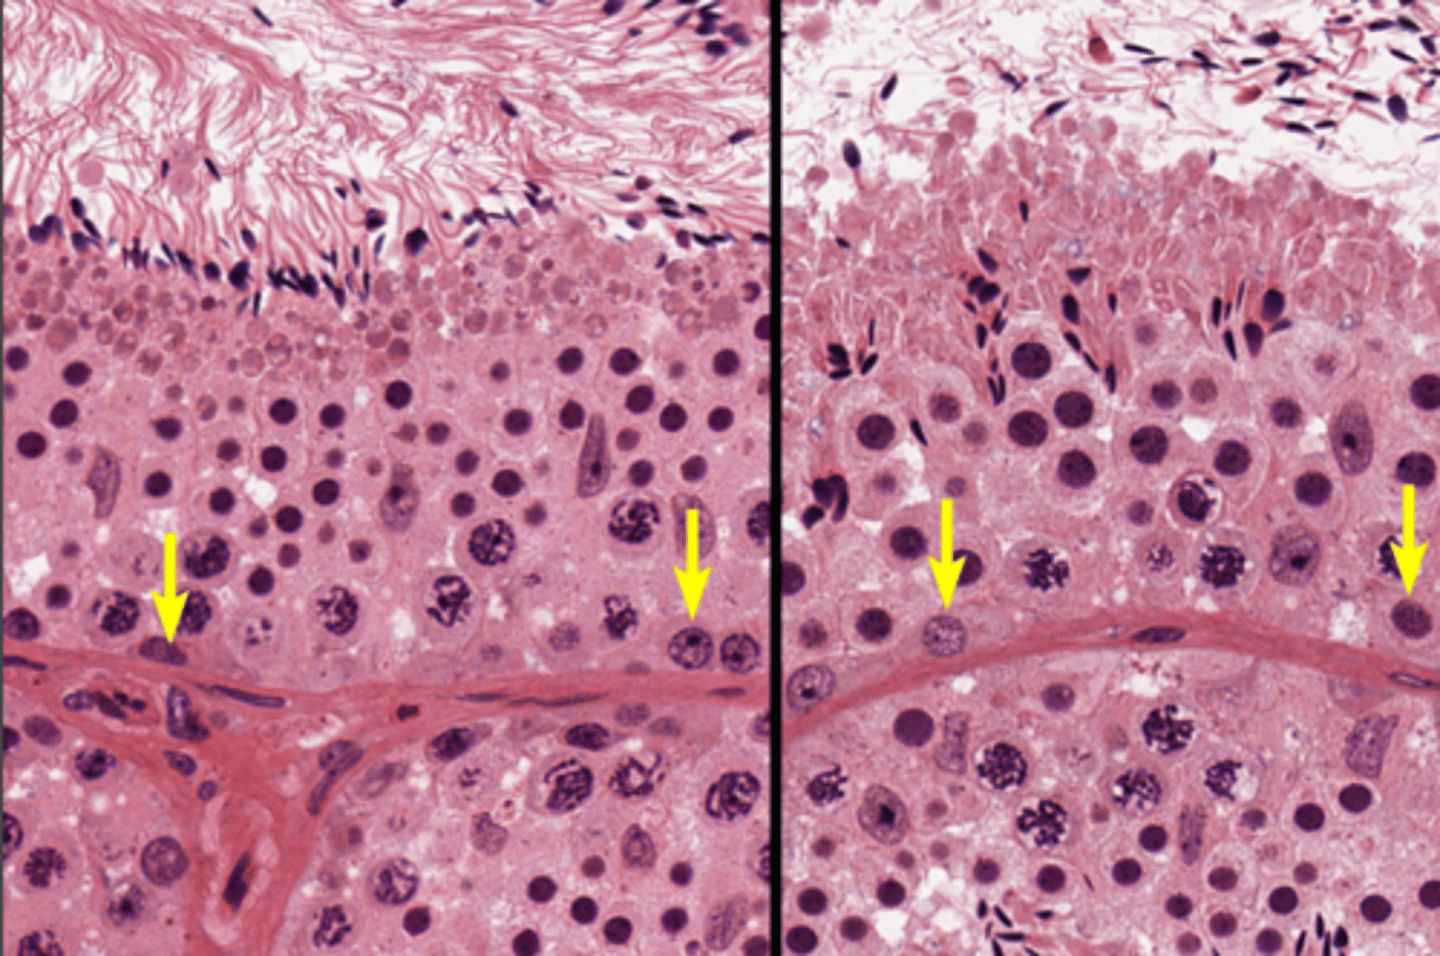

Seminiferous tubules

Seminiferous tubules

Seminiferous tubules

Spermatogenesis

Spermatogenesis

Spermatogonia

Primary spermatocyte

Primary spermatocyte

Spermatid (early)

Spermatid (late)